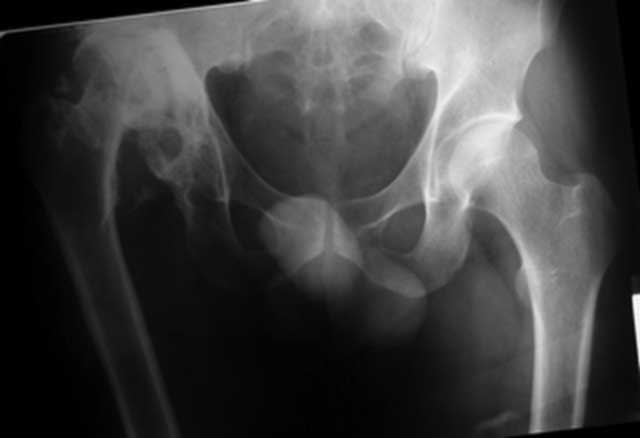

Застарелый вывих бедра (продолжение темы)

репозиция 3 нед, артропластика Corail-Duraloc